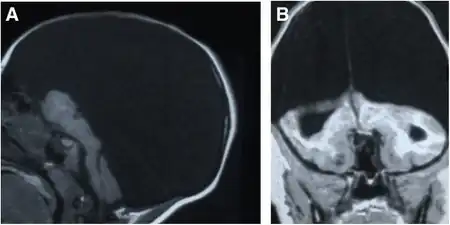

An accurate, confirmed diagnosis is generally impossible until after birth, though prenatal diagnosis using fetal ultrasonography (ultrasound) can identify characteristic physical abnormalities. After birth, diagnosis may be delayed for several months because the infant's early behavior appears to be relatively normal. The most accurate diagnostic techniques are thorough clinical evaluation (considering physical findings and a detailed patient history); advanced imaging techniques, such as angiography, computerized tomography (CT scan), and magnetic resonance imaging (MRI); and (more rarely) transillumination.[3] However, diagnostic literature fails to provide a clear distinction between severe obstructive hydrocephalus and hydranencephaly, leaving some children with an unsettled diagnosis.[7]

Once destruction of the brain is complete, the cerebellum, midbrain, thalami, basal ganglia, choroid plexus, and portions of the occipital lobes typically remain preserved to varying degrees. The cerebral cortex is absent; however, in most cases, the fetal head remains enlarged due to increased intracranial pressure, which results from inadequate reabsorption of the cerebrospinal fluid produced in the choroid plexus.[6]